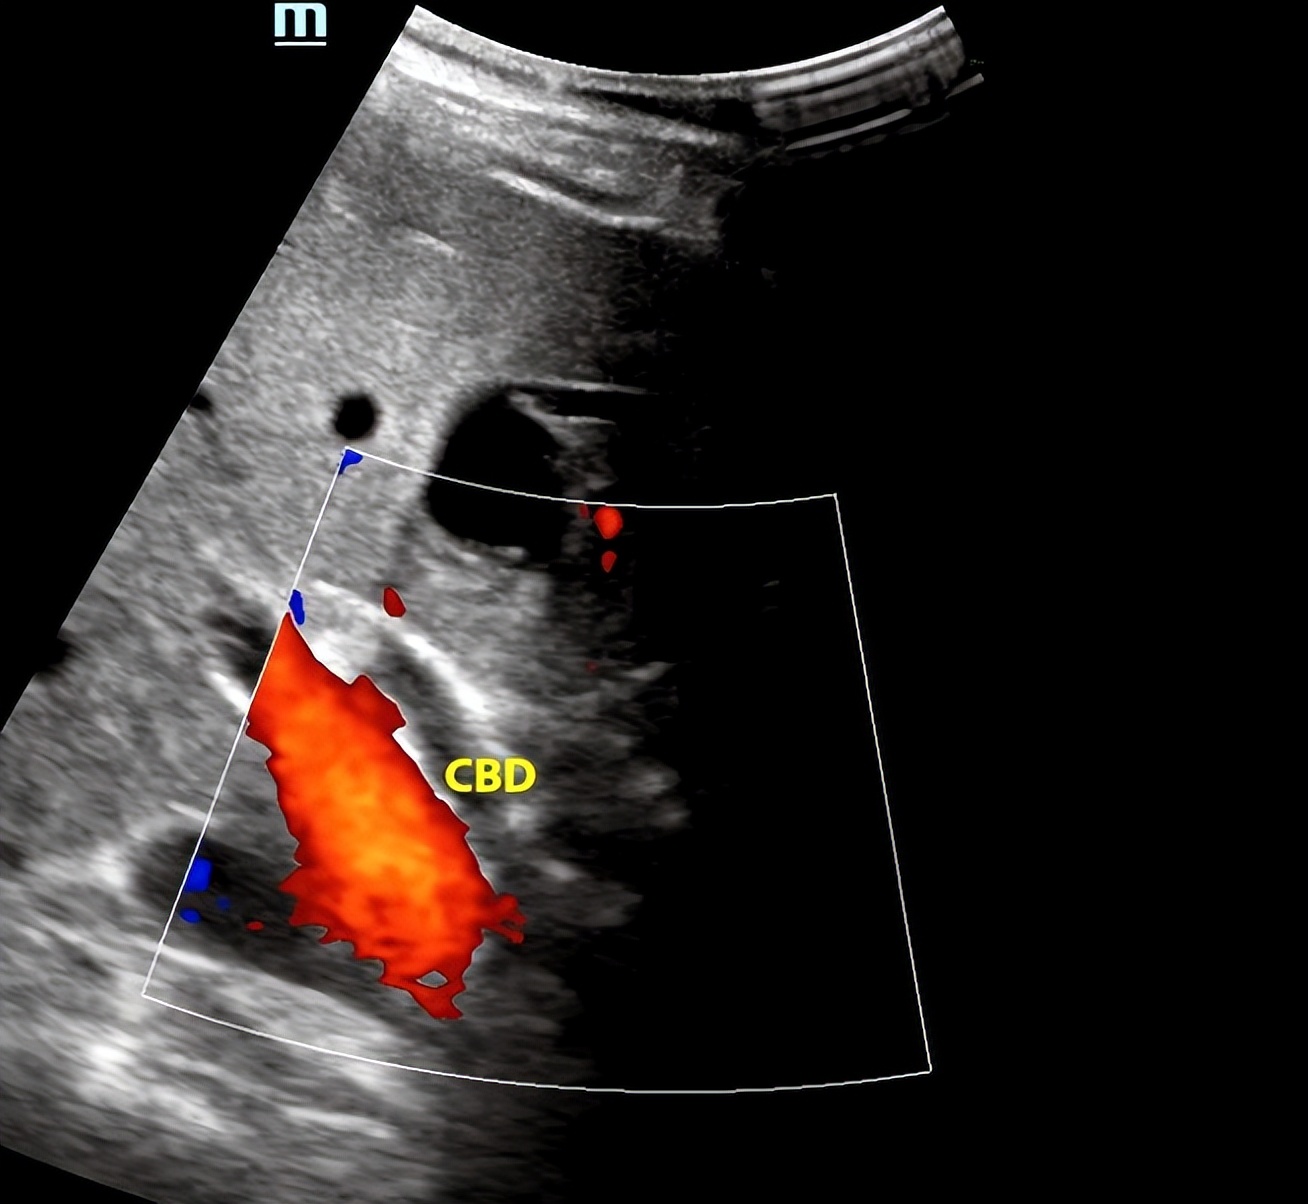

改变体位有时是真的香,对于胆囊和肝外胆管,平卧位时,患者稍微有点肉肉就不好显示,左侧卧位轻轻一扫,诶,清清楚楚,这就很棒。